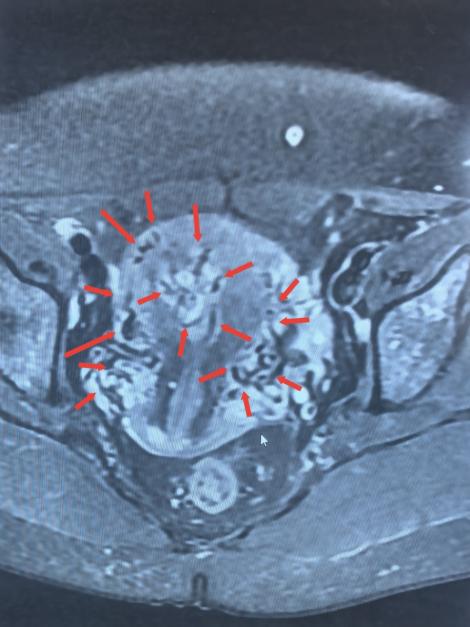

術(shù)前檢查影像

檢查結(jié)果很快傳來,B超結(jié)果顯示宮腔內(nèi)殘留組織伴豐富血流,高度懷疑“子宮動(dòng)靜脈瘺”;隨后的MRI檢查進(jìn)一步證實(shí),患者宮腔內(nèi)不僅有異常病灶,鄰近子宮前壁還出現(xiàn)多發(fā)流空信號——這意味著子宮動(dòng)脈與靜脈之間形成了異常通道,動(dòng)脈血直接涌入靜脈,一旦通道破裂,就可能引發(fā)難以控制的致命性大出血。